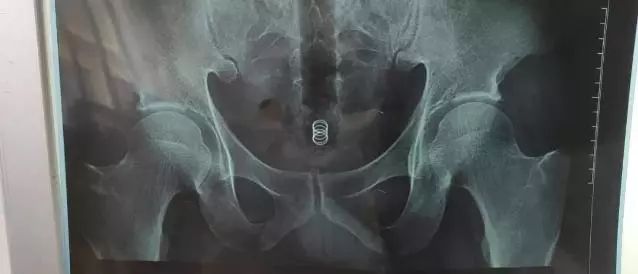

随后,医生给其进行了拍片。片子显示,该男子从肛门进入直肠的,是一长条类管子。

并且可以从片子上看出,体内异物已深深陷入直肠,如果不及时处理会导致直肠感染,肠梗阻,肠穿孔等一系列并发症,甚至危及生命。